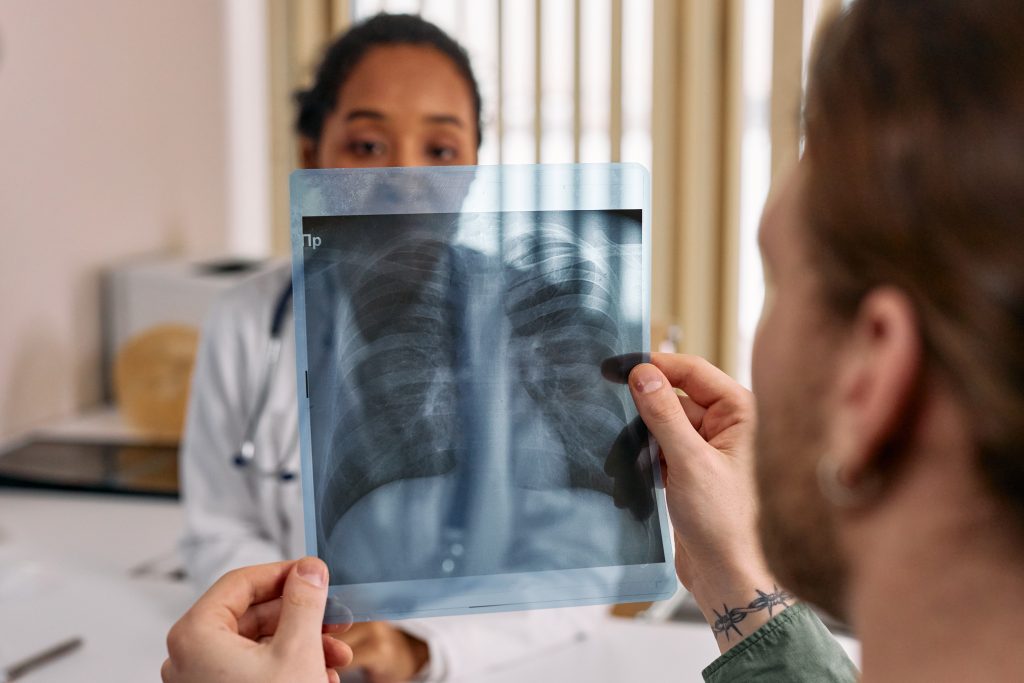

Do you have a surgery scheduled, but you’re not sure how to prepare? We understand the time leading up to surgery can be stressful, so we have a few tips that can help you overcome the mental and physical stress that comes with surgery. Preparing Mentally For Surgery If you’re preparing for surgery, you’ve likely […]